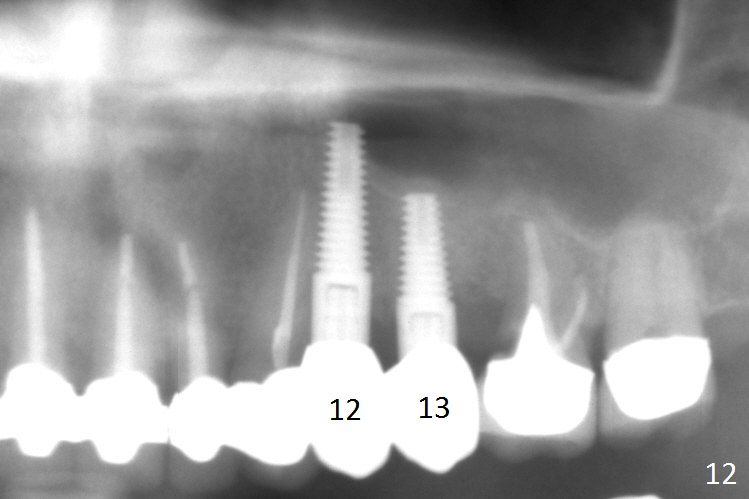

The distal threads appear not covered by the bone 2.5 months postop (Fig.11 >). His oral hygiene is excellent with healthy gingiva around the implant when the permanent crown is cemented. Panoramic X-ray is taken 3 years and 1 year 5 months post cementation for #12 and 13, respectively (Fig.12). The bone density around the implant at #13 increases 2 years 6 months post cementation (Fig.13 *). The bone density of the sinus lift (Fig.14,15 *) is essentially the same as that of the bone buccal (B) and palatal to the implant 4.5 years post cementation. The upper left panel is a 3D view from the sinus.